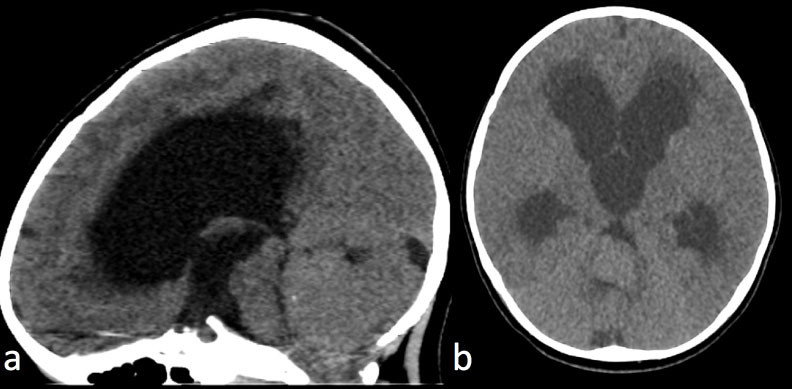

Figure 1: CT of intracranial infratentorial Ependymoma.

Non contrast CT Head a) Sagittal view; b) Axial view.

3-year-old with truncal ataxia. Non contrast CT head demonstrates a large isodense posterior fossa mass originating from the fourth ventricle and resulting in severe hydrocephalus with transependymal CSF absorption. A punctate calcification is present in the superior portion of the mass.

The MRI features of ependymomas include low T1, high T2, and iso- to high fluid-attenuated inversion recovery (FLAIR) signal intensity due to their increased myxoid component [7]. Ependymomas are heterogeneously enhancing masses that demonstrate avid enhancement of the soft tissue components with adjacent areas of little to no enhancement. In the posterior fossa, ependymomas typically arise in the floor of the fourth ventricle and the pliable nature of these tumors can result in extension of the lesion from the fourth ventricle through the foramen of Luschka or foramen of Magendie [6] (Figure 1 and Figure 2). See Table 3.